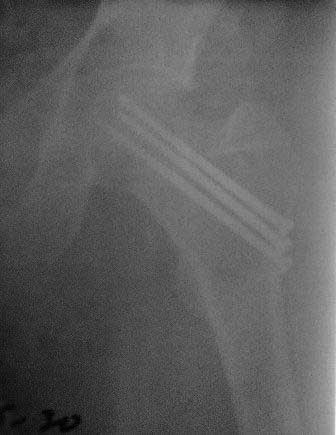

[Ortho] Ложный сустав шейки бедра

Обратился б-ной около 40 лет, три месяца назад оперирован в г.Алмате. При осмотре ходит с двумя костылями, беспокоят постоянные боли, симптом прилипшей пятки положительный, посмотрел под Р-скопией; сращения нет.

P.S.   Р-снимки сразу после операции,  и вчерашные.

Имя     : 2.jpg